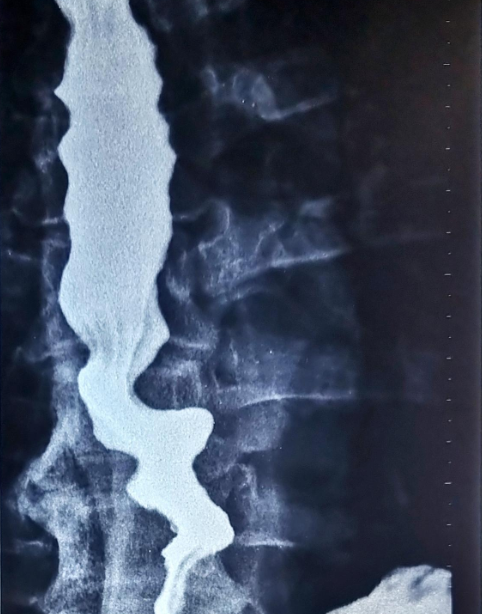

Acid ingestion (HCL). Diffuse burns and contraction/shrinkage of both the esophagus and stomach (Courtesy Dr. V. Penopoulos)